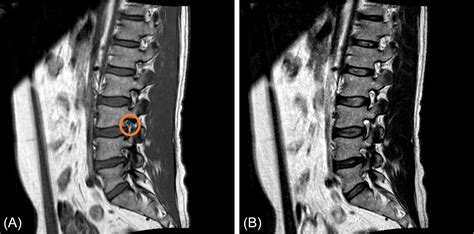

In the world of medical imaging, a normal lumbar MRI indicates that the radiologist did not find any significant anatomical abnormalities that would explain severe pain or nerve compression. Specifically, a normal report suggests that the structural components of your lower back are within expected parameters.

• Intervertebral Discs: They appear hydrated (not dried out or "black"), are of normal height, and do not bulge or herniate into the spinal canal.

• Spinal Canal: There is no significant narrowing (stenosis) that would compress the spinal cord or nerve roots.

• Vertebrae: The bones show no evidence of fractures, tumors, or significant degenerative changes.

• Ligaments and Soft Tissue: There is no evidence of inflammation, abnormal masses, or thickening that would impede normal function.

Essentially, a normal scan confirms that there is no "smoking gun"—no obvious physical damage that necessitates emergency surgery or points to structural disease. However, it is vital to remember that radiographic findings do not always correlate perfectly with clinical symptoms. Many people walk around with "abnormal" findings on an MRI and feel no pain, while others have significant pain despite having a perfectly normal lumbar MRI.